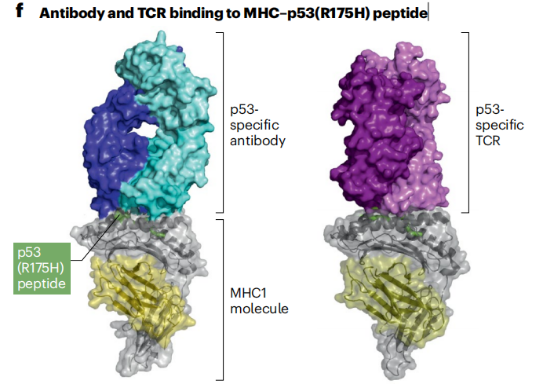

规避肿瘤特异性抗原缺乏的方法可以通过多种抗原的组合靶向,其次靶向仅在肿瘤中共表达而不在健康组织中共表达的抗原组合可能提供一种可行的治疗途径,目前学界正在寻找靶向肿瘤特异性抗原,细胞内抗原,以及肿瘤微环境中的抗原。靶向低密度抗原仍然是一个挑战,研究者正在探索使用优化的抗体工程来解决这个限制,从而能够有效靶向新抗原和其他低丰度靶标。

针对p53(R175H)肽与主要组织相容性复合体(MHC)结合的抗体,与分子肽平行结合,与之形成对比的是,特异性T细胞受体(TCR)则与肽垂直结合。此外,该抗体对p53(R175H)新抗原的亲和力比相应的TCR高约100倍。可能是不同的结合方式导致了抗体的特异性和高亲和力,这个发现为开发新的治疗性抗体提供了基础。